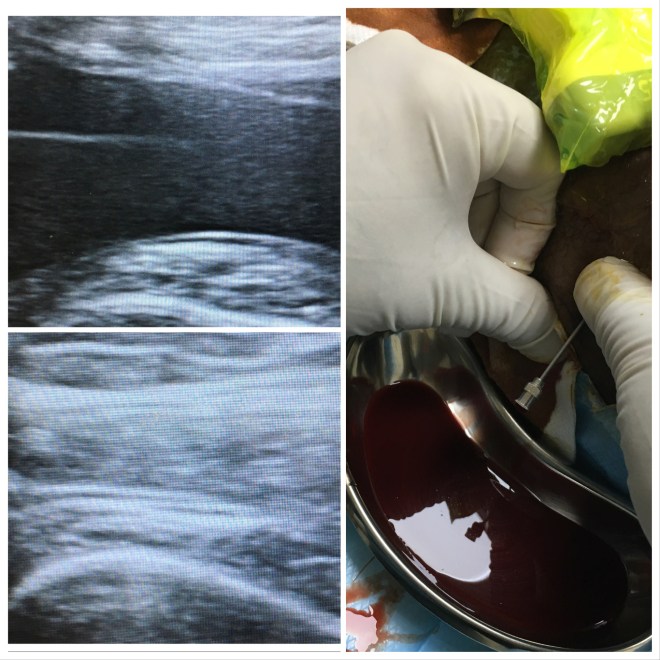

Hemarthrosis Knee